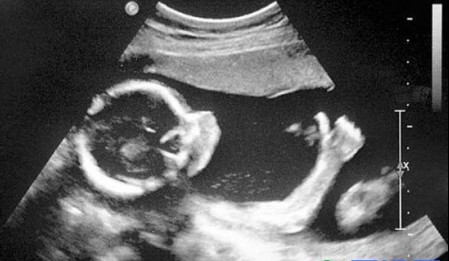

男婴会在子宫里产生勃起,女婴也会*慰自**

大多数妈妈不喜欢考虑她们的男婴能否会勃起,即便她们是很开放的年轻人,但事实是许多男婴当他们还在子宫里的时分就开端犯错了。上面的这幅图片是独一被超声波图像抓拍到的男婴勃起图片,而且还不只是男孩,女孩也会有相似*慰自**的状况。只不过只要男孩的勃起能够被超声波照到而已。假如在怀孕期间有*生活性**似乎有点令人毛骨悚然,想想你的孩子正在做一些当你在*爱做**时大脑中所想的事情吧。